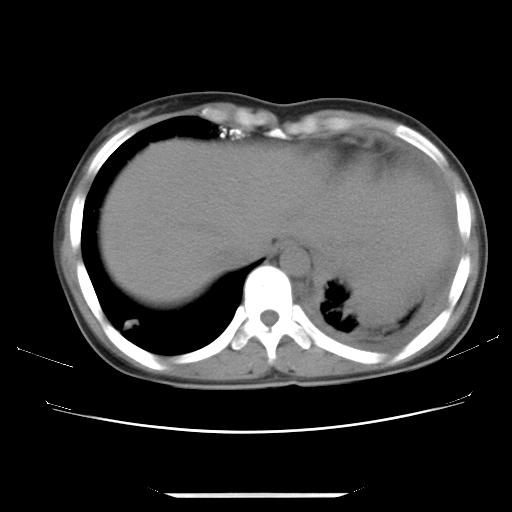

女,29岁,胸部不适,在外院胸片提示胸腔积液,到我院ct检查。

纵膈窗

左肺上叶不张,左侧胸水,叶间裂积液,纵隔淋巴结,脾脏钙化,考虑左肺上叶支气管内膜结核,结核性胸膜炎,脾结核

支持两肺继发性肺结核,左侧胸膜腔包裹性积液、胸膜肥厚,脾内多发钙化(结核钙化)。

支持 两肺继发性肺结核,左侧胸膜腔包裹性积液、胸膜肥厚;脾内多发钙化(结核钙化)。

两肺继发性肺结核,左侧胸膜腔包裹性积液、胸膜肥厚;脾内多发钙化(结核钙化)。支持!

左肺上叶不张,左侧胸水,叶间裂积液,纵隔淋巴结,脾脏钙化,考虑左肺上叶支气管内膜结核,结核性胸膜炎,脾结核。支持!